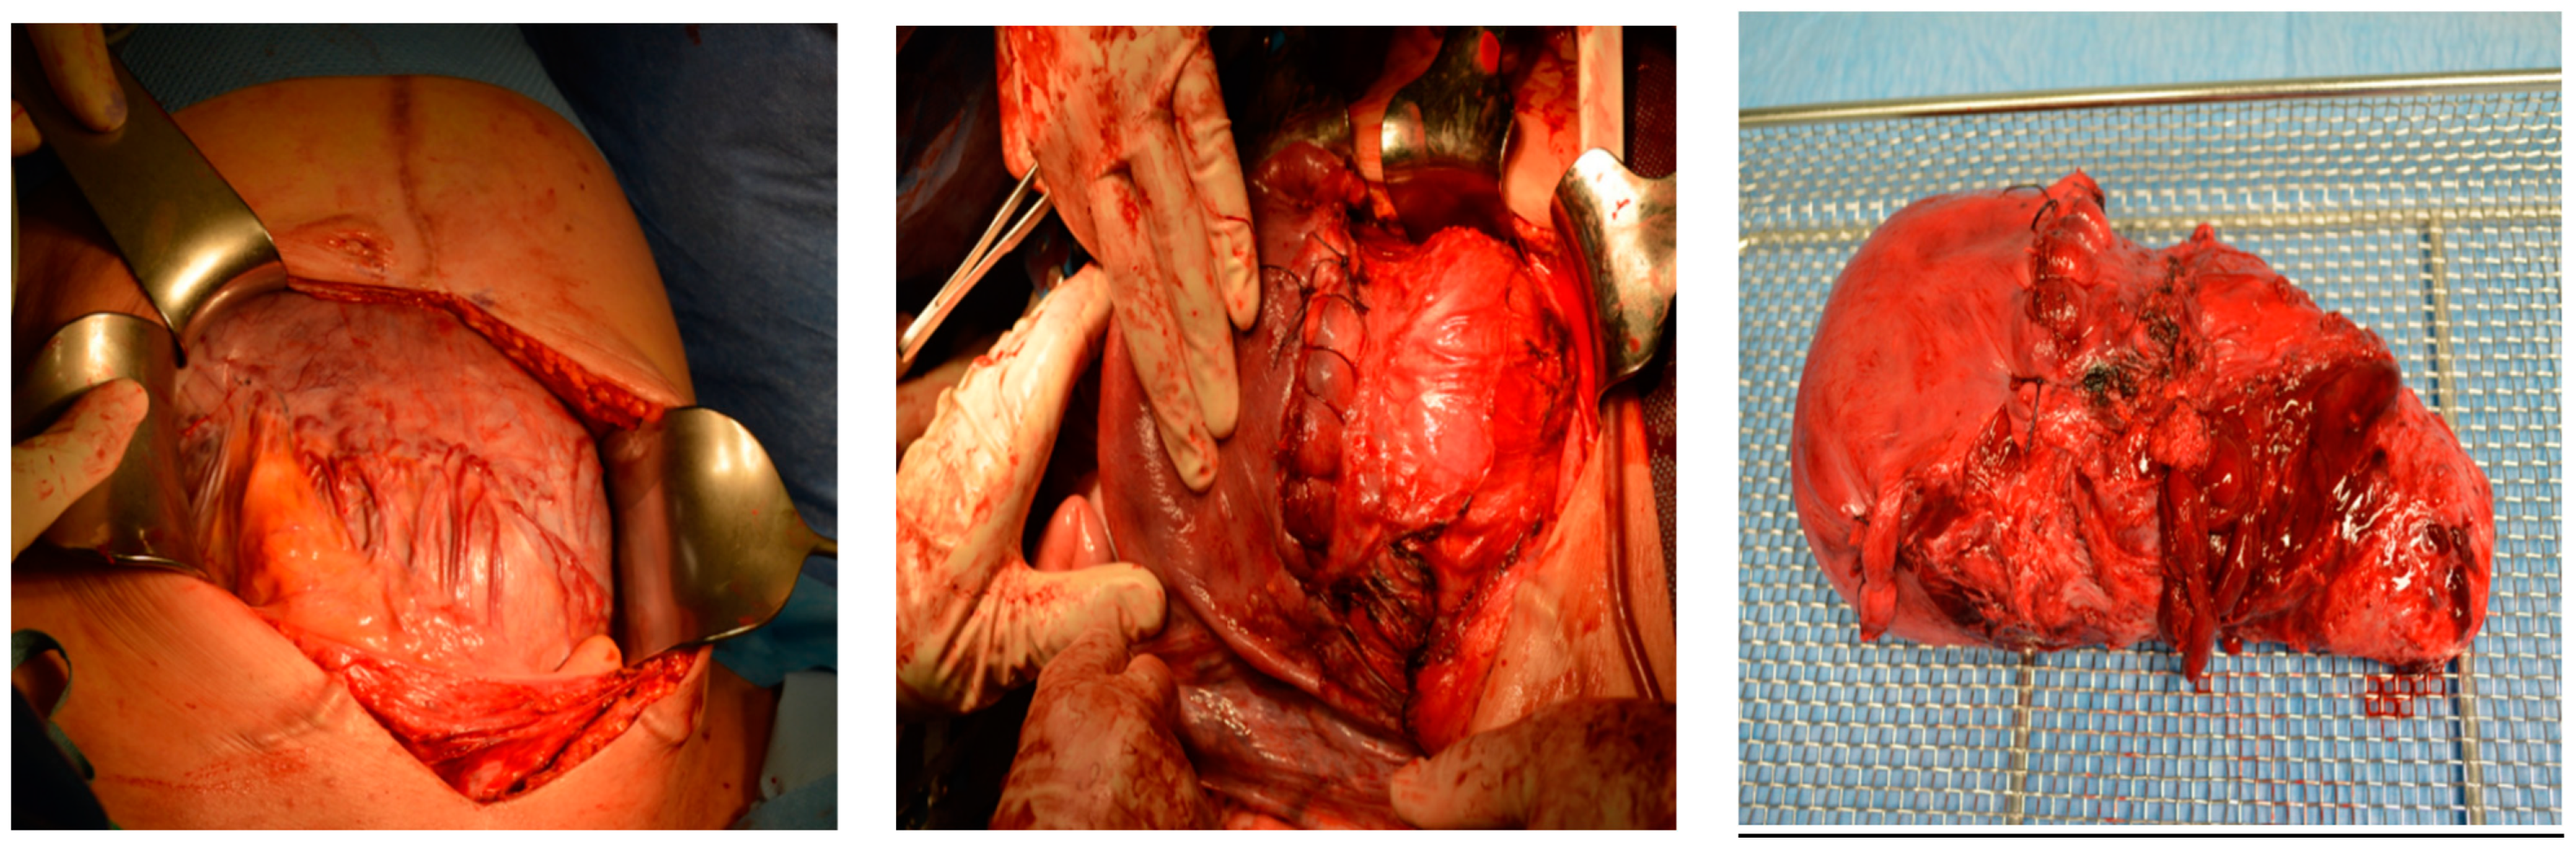

Intraoperative findings (Figure 10):

Figure 10.

depict the uterus after hysterectomy with placenta previa and increta extending to the serosa. These images show the following findings:

- The uterus following a hysterectomy illustrates the presence of placenta previa with increta extending to the outermost layer of the uterine wall (serosa).

This confirms the suspected diagnosis of placenta previa with placenta increta, which necessitated the hysterectomy procedure to manage the condition.